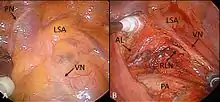

Подальший розвиток напрямку- відеоасистована торакоскопія ( англ. videoassisted thoracoscopic surgery , VATS ). Залежно від типу втручання, в деяких випадках його можна провести за допомогою гнучких ендоскопів .

До 1990-х років ці втручання частіше всього використовувались лише для діагностики, або для лікування таких захворювань, як пневмоторакс, плевральний випіт або емпієма плеври. Завдяки розробці безпечних методів з'єднання легеневої тканини та судин, малоінвазивна торакальна хірургія тепер може застосовуватися для видалення ураженого відділу легені ( резекція легені ), або видалення метастазів в лімфатичних вузлах, та взяття проб для гістологічного дослідження. Операція найчастіше служить для підтвердження, або виключення діагнозу раку. Вона виконується під візуальним контролем, при цьому зображення камери висвічується на моніторі. Зазвичай робляться три окремі надрізи приблизно 2-3 см довжини. а інструменти вводять між ребрами. Для виконання лобектомії за допомогою ВАТС, не повинно бути широких плевральних спайок і пухлина не має знаходитись поруч з воротами легень . До протипоказань можна також віднести, ожиріння, попередньо проведену хіміотерапію або променеву терапію (в рамках неоад'ювантної терапії) в анамнезі .